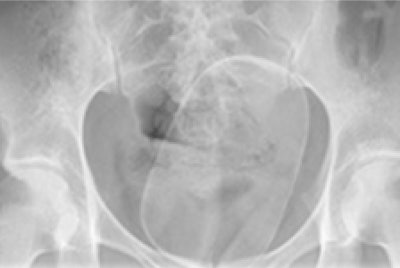

In another case, a 24-year-old woman was found to have a foreign body lodged within her vaginal cavity. On x-ray, a solitary well-defined radiopaque density was lying within the pelvis, outside of the bowel lumen. The patient required examination under anesthetic, episiotomy, suprapubic pressure, and manual delivery of a plastic cylindrical mass weighing 288 g.